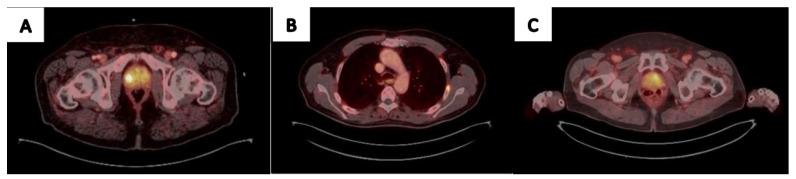

Prostate-specific membrane antigen (PSMA) PET use in prostate cancer treatment has recently become a routinely used imaging modality by urologists. New, established data regarding its performance in different stages of prostate cancer, as well as gaining clinical knowledge with new tracers, drives the need for urologists and other clinicians to improve the utilization of this tool. While the use of PSMA PET/CT is more common in metastatic disease, in which it outperforms classical imaging modalities and drives treatment decisions and adjustments, recently, it gained ground in localized prostate cancer as well, especially in high-risk disease. Still, PSMA PET/CT might reveal lesions within the prostate or possibly locoregional or metastatic disease, not always representing true cancer when utilized in earlier stages of the disease, potentially adding diagnostic burden and changing treatment decisions. As urological treatment options advance toward focal treatments in localized organ-confined prostate cancer, recent reports suggest the utilization of PSMA PET/CT in treatment planning and follow-up and even when choosing active surveillance. This review aims to reveal the current perspective of urologists regarding its daily use.

前列腺特异性膜抗原(PSMA)PET在前列腺癌治疗中的应用最近已成为泌尿外科医生常用的成像方式。有关其在前列腺癌不同阶段表现的新的、既定数据,以及随着新示踪剂获得的临床知识,促使泌尿外科医生和其他临床医生提高对该工具的利用。虽然PSMA PET/CT在转移性疾病中的应用更为常见,在转移性疾病中它优于传统成像方式并推动治疗决策和调整,但最近它在局限性前列腺癌中也得到了应用,尤其是在高危疾病中。然而,PSMA PET/CT可能会在前列腺内发现病变,或者可能发现局部或转移性疾病,在疾病早期使用时并不总是代表真正的癌症,这可能会增加诊断负担并改变治疗决策。随着泌尿外科治疗方案朝着局限性器官局限性前列腺癌的局部治疗发展,最近的报告表明PSMA PET/CT在治疗规划和随访中甚至在选择主动监测时都有应用。本综述旨在揭示泌尿外科医生对其日常使用的当前观点。